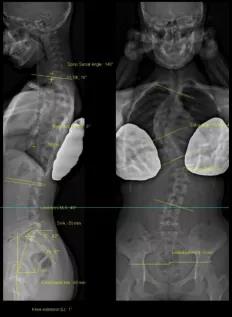

脊柱側(cè)彎